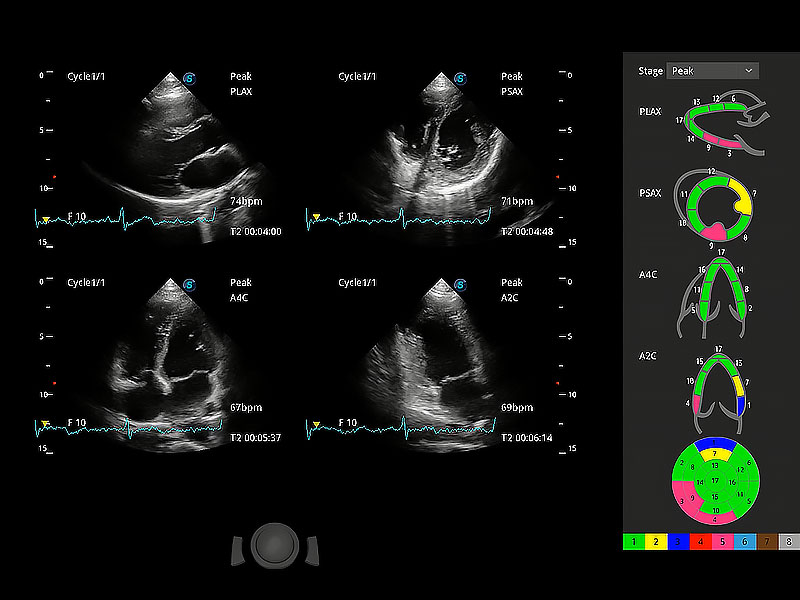

ProPet 80 配備了豐富的心臟探頭群、先進(jìn)的成像技術(shù)和專業(yè)的心臟測量工具,可幫助動物醫(yī)生為不同體型和生理結(jié)構(gòu)的動物提供心臟和心肌功能的全面評估。

實(shí)時用顏色表示心肌組織運(yùn)動,觀察和定量組織的運(yùn)動情況,對快速檢測與評估心肌的灌注和活性、電傳導(dǎo)及心肌收縮和舒張功能等均能提供重要的診斷信息。

通過心肌識別技術(shù)與二維斑點(diǎn)追蹤技術(shù)相結(jié)合,對心臟的超聲圖像進(jìn)行量化分析。計算心肌17個節(jié)段的應(yīng)變、應(yīng)變率、速度、位移等,并通過牛眼圖的形式進(jìn)行呈現(xiàn)。

通過360度任意調(diào)節(jié)3條M型取樣線,在同一心動周期上觀察心臟不同位置的運(yùn)動曲線,得到準(zhǔn)確的心功能測量數(shù)據(jù),有效評估心肌運(yùn)動及左心室功能。

具備多種協(xié)議可選,同時支持17階段劃分法和專業(yè)的SE報告。